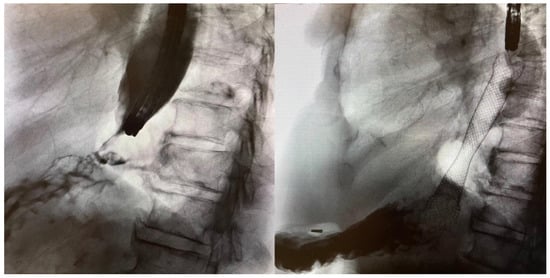

4. Pre-Procedural Patient Evaluation

5.3. Endoluminal Insertion of SEMS